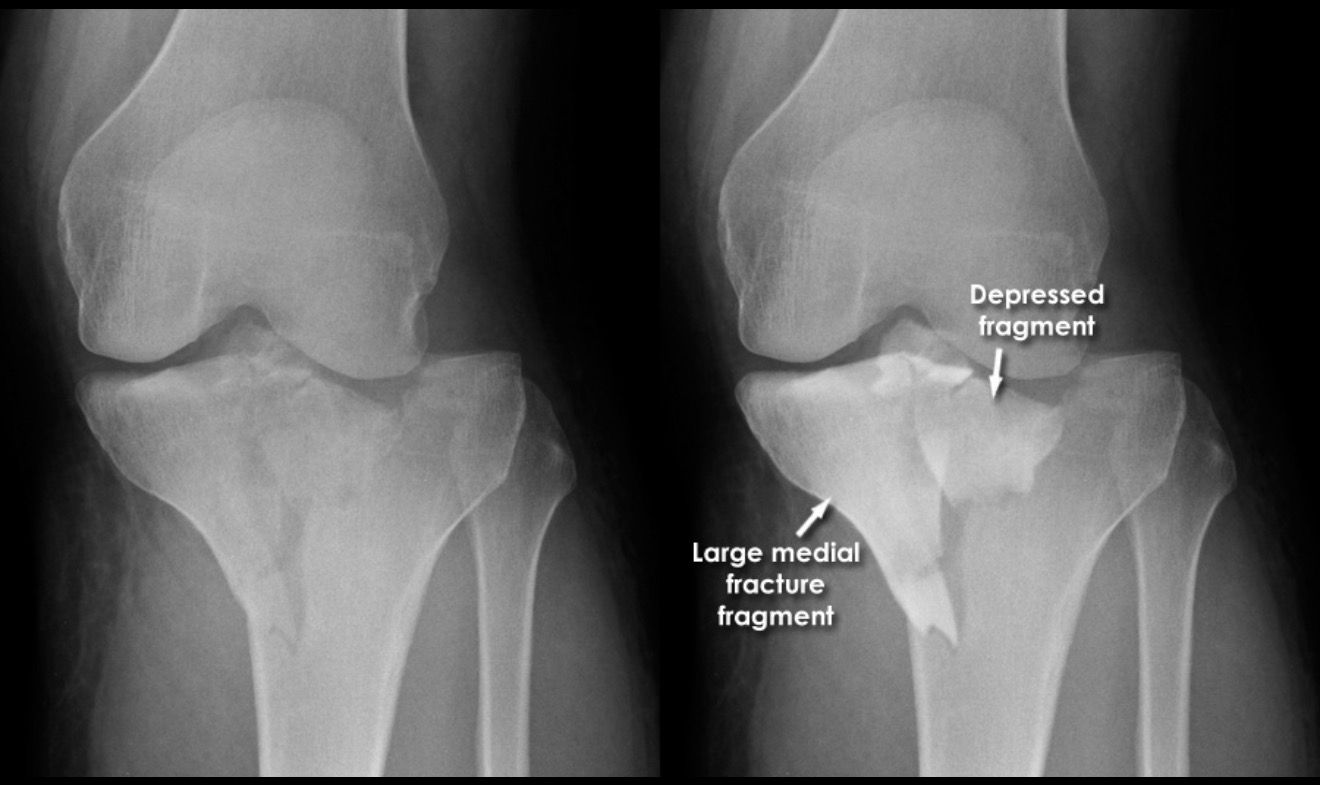

2. Fractures Involving the Joint Surface

Fractures like tibial plateau fractures directly affect the knee joint. Even a small misalignment can lead to arthritis later. Robotic assistance ensures near-perfect joint restoration.

Robotic assisted knee surgery procedure image 2 Robotic assisted knee surgery procedure image 3 Robotic assisted knee surgery procedure image 4 Robotic assisted knee surgery procedure image 5